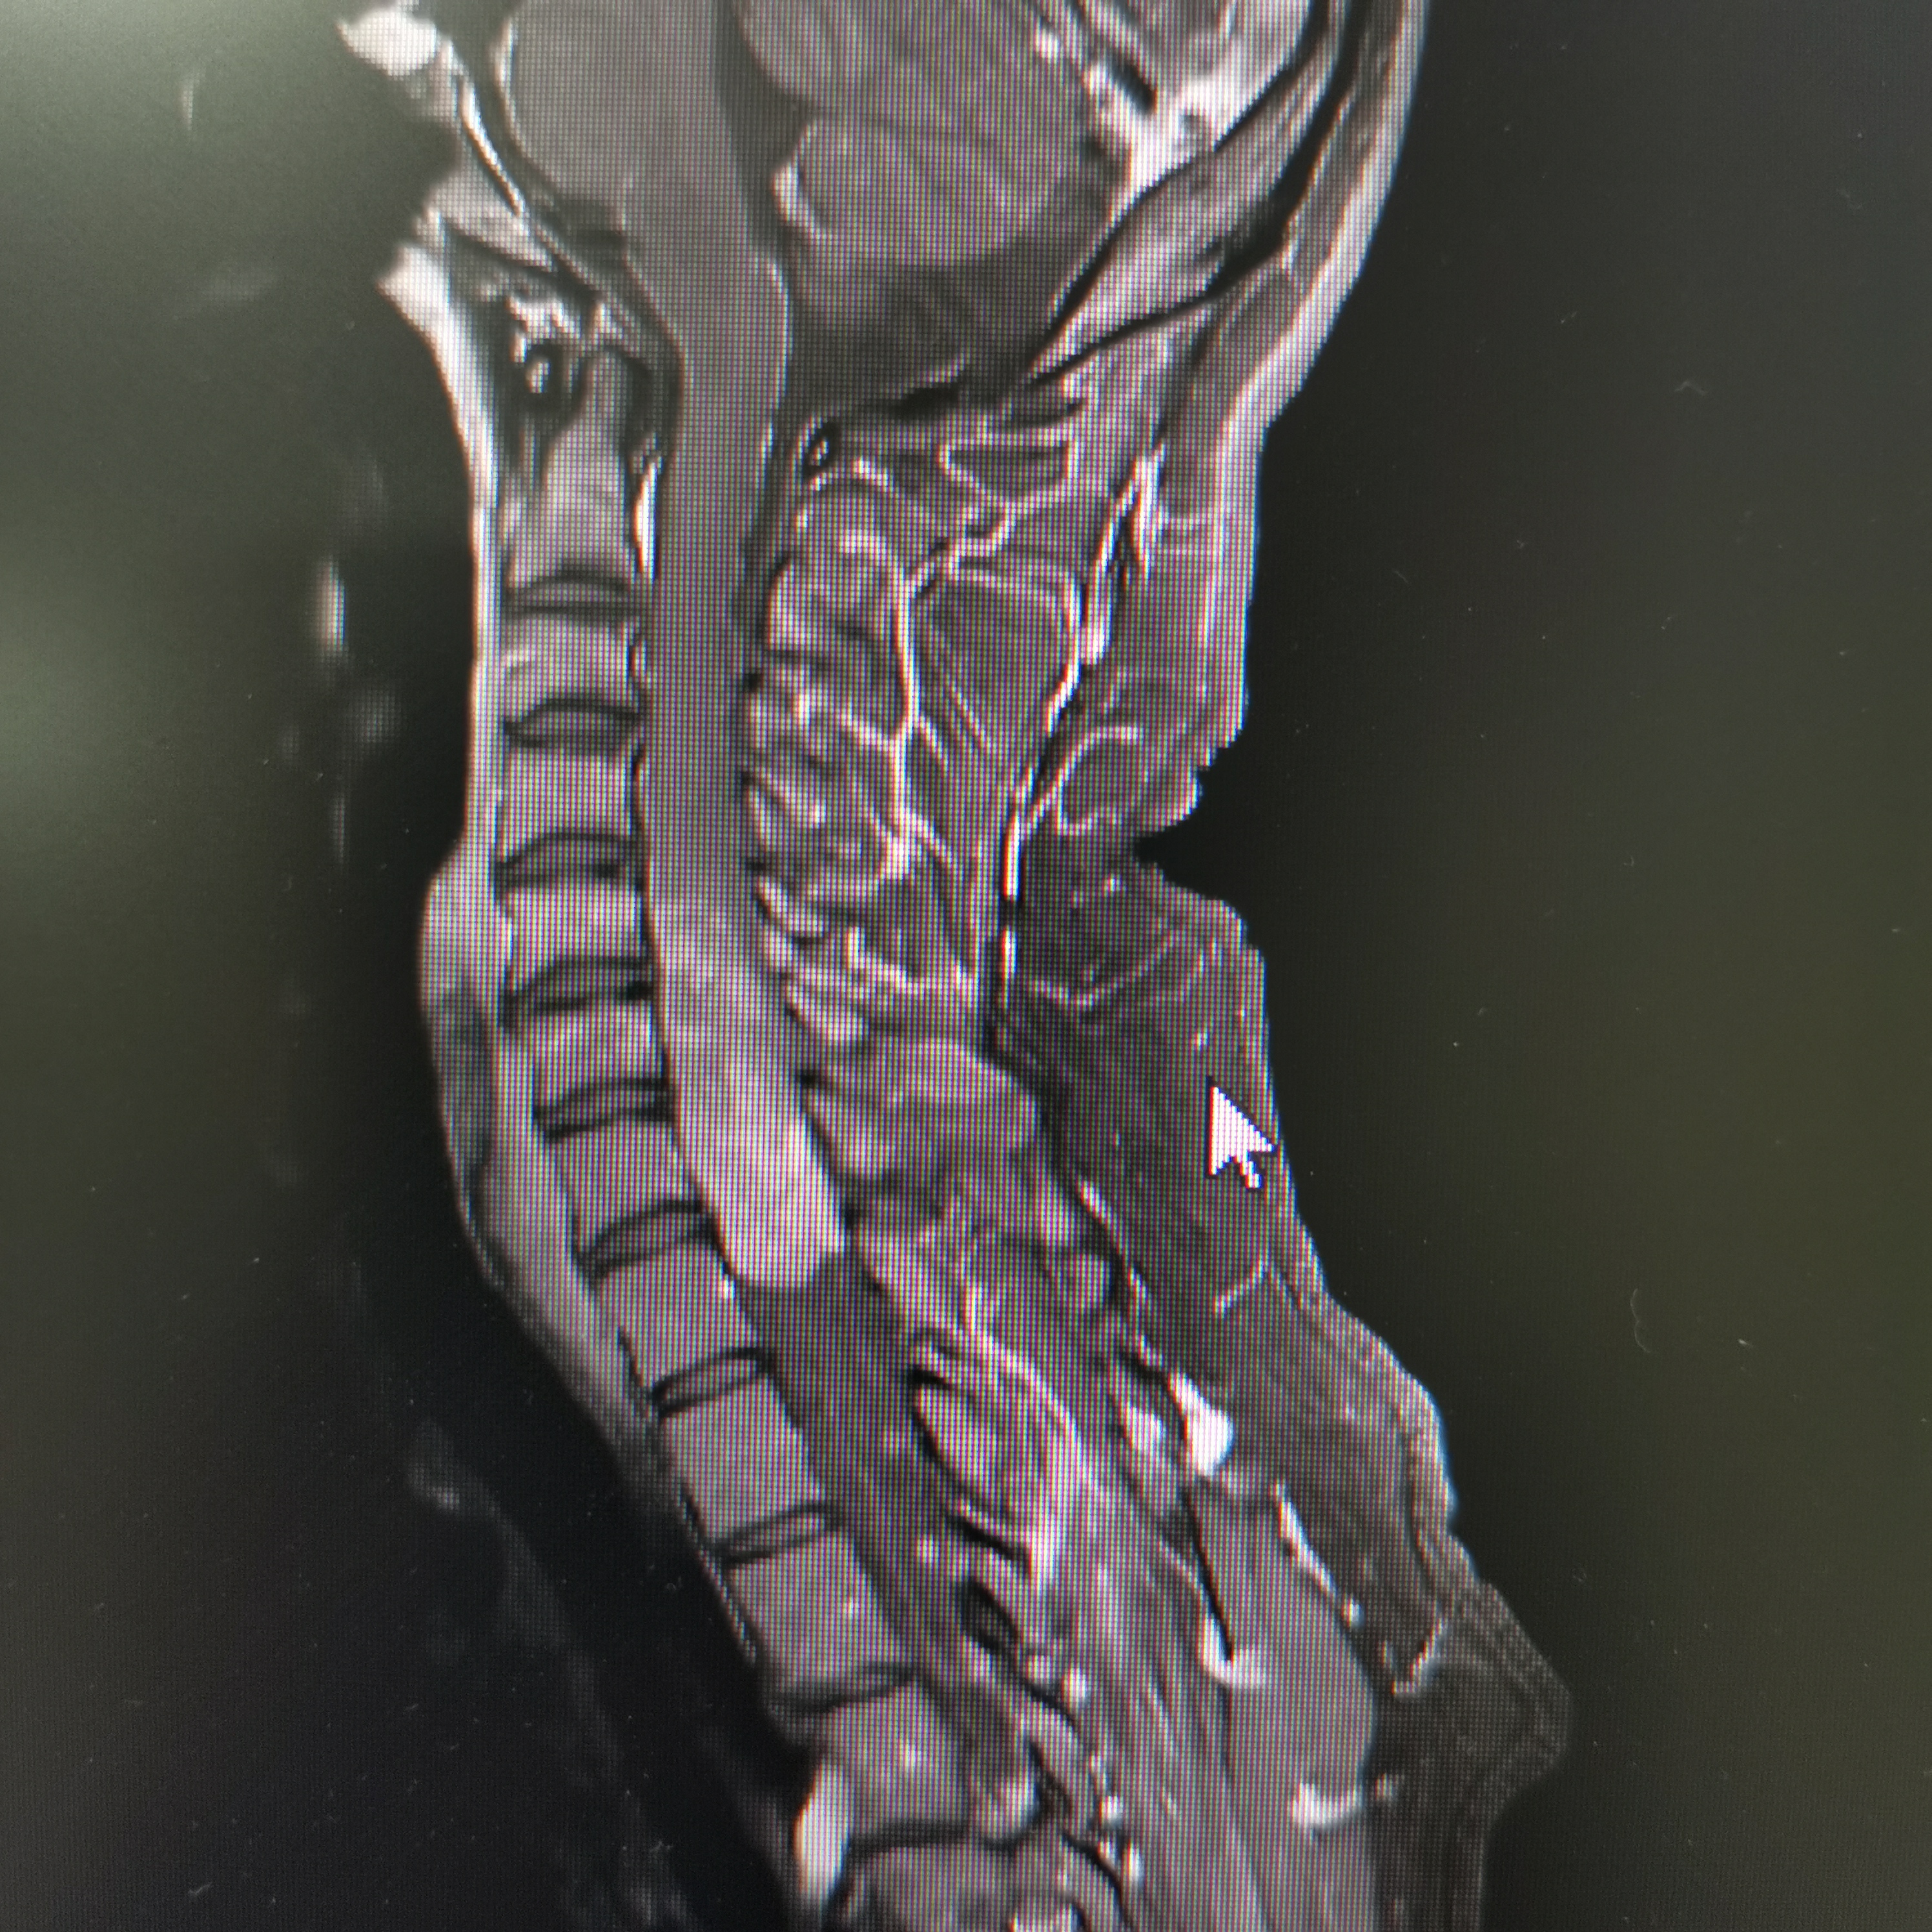

脊髓脊柱-脊髓脊柱肿瘤

神经纤维瘤病的治疗需要综合考虑患者的病情、症状、年龄、身体状况等因素,制定个性化的治疗方案。